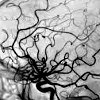

Ангиография. Рентгенологическое исследование кровеносных сосудов с использованием контрастного вещества. Опираясь на способность определенных растворов не пропускать рентгеновские лучи, ангиография позволяет оценить расположение и функциональное состояние кровеносных и лимфатических сосудов, а также скорость кровотока. Он может обнаружить врожденные аномалии, пораженные участки (например, в случае нарушений кровообращения из-за тромбоза или эмболии, нарушения целостности сосудов), кровообращения в случае повреждения крупных сосудов и сосудистые сети в новообразованиях.

Ангиография позволяет диагностировать нарушения кровообращения по геморрагическому типу (аневризма, сосудистые дивертикулы, ангиомы) и ишемическим (атеросклеротические изменения, нарушения кровотока, сосудистые деформации). Кроме того, во время ангиографии обнаруживаются изменения сосудистого рисунка, характерные для доброкачественных и злокачественных новообразований головного мозга. Для увеличения информативности наряду с классической рентгенографией используется КТ сосудов, что позволяет получать послойные изображения сосудов головного мозга и его трехмерное изображение, создаваемое компьютером.